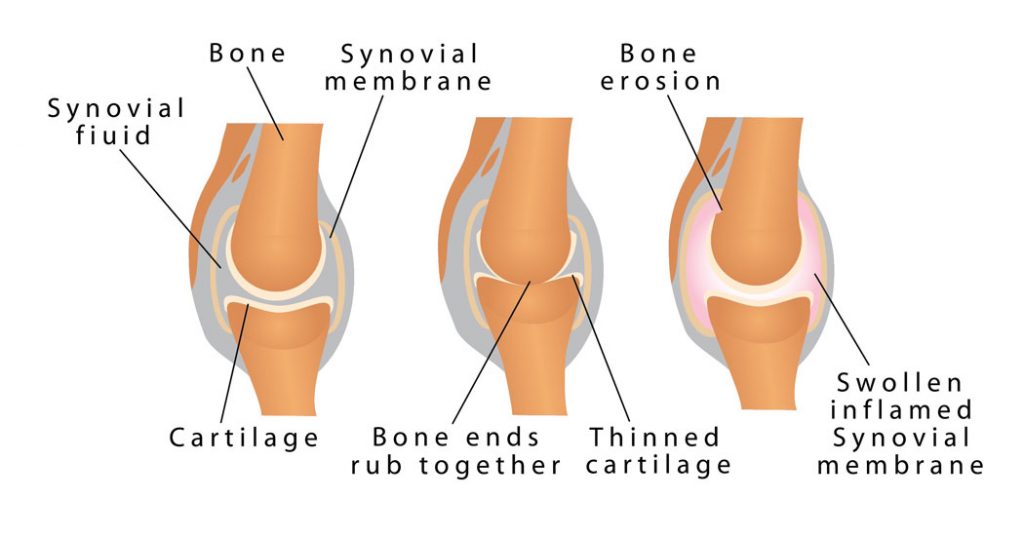

Finger arthritis is an inflammatory disorder that can occur in many different ways. It can be systemic where your body will attack itself in the case of Rheumatoid Arthritis (RA) or it may occur as a result of wear and tear, Osteo Arthritis (OA). While both of these conditions are painful and involve swelling and the de generation of the cartilage insie the joints of the finger, their cause is very different. At Action Rehab Hand Therapy Clinic our Hand Therapists assess and treat a majority of patients who suffer from Osteo Arthritis (wear and tear of the joints) which often occurs as a result of a sporting or repetitive job or task such as gardening. This type of arthritis is very common and can be easily treated. Finger arthritis is painful and it is debilitating and can cause deformities if left untreated. At Action Rehab Hand Therapy Clinic our Hand Therapists, Physiotherapists and Occupational Therapists are experienced in reading x-rays and assessing your hand for arthritis and joint degeneration.

Characterised by deformity, swelling, pain, stiffness and achy fingers caused by degeneration of the joint. Often pain in these joints can result in the development of Herbeden’s Node, a painful fluid sack and swelling. Action Rehab Hand Therapy Clinic can assess and treat the pain and help you manage your symptoms through a variety of techniques including waterproof removable splinting, education, exercises, joint protection techniques and heat treatments.

Ulnar Drift

It may be due to the presence of Rheumatoid Arthritis (RA). RA can cause the erosion of tendon and joint cartilage and results in your fingers being pulled towards your little finger (ulna side) of your hand. An MCP ulnar drift splint may help you to reduce your pain, increase your function and help make a fist. A resting night splint can help to prevent further ulnar drift. At Action Rehab Hand Therapy Clinic we have experience in both of these splints and are here to help you.